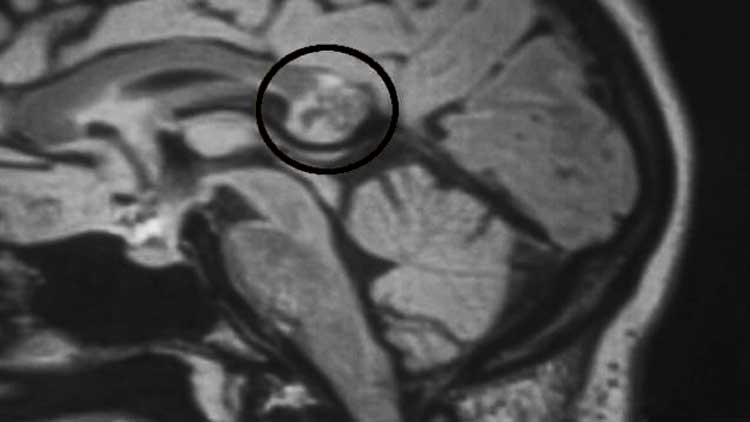

Tenía un embrión en el Cerebro